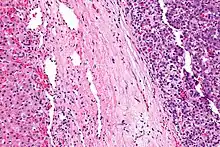

| Micrograph of a hepatoblastoma. H&E stain. | |